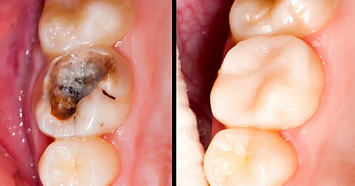

When teeth have decay, cracks or cavities, it is recommended that you get dental radiographs taken to check and confirm the depth of the decay or cavity. That way we can diagnose the condition, and therefore depending on how deep it is, we can do a filling. If the decay has reached the pulp, then it is advisable to do a root canal treatment to eliminate pain and save the tooth.

Root canal treatment (also called Endodontics) is needed when there is an infection in your pulp, through tooth decay or the tooth is damaged by an injury to your mouth. This infection may spread through the root canal system, which could eventually lead to a dental abscess, causing a great deal of discomfort or pain. If root canal treatment is not carried out, the tooth may need to be taken out. Our Dentist can perform root canal treatment to stop the infection from spreading and will preserve as much of your tooth as possible. Using specific techniques and advanced equipment, you will receive a local anaesthetic, and the treatment overall should feel no different to having an ordinary filling placed. The aim of the treatment is to remove all infection from the root canal. The root is then cleaned and filled to prevent any further infections. A temporary filling is put in on the first appointment, and the tooth is left to settle. The tooth is checked at a few days later, and when all the infection has cleared, the tooth is permanently filled. Root canal treatment is a skilled and time-consuming procedure, and most courses of treatment will involve two or more visits. To keep your mouth in shape, we recommend you come in for regular hygiene appointments and dental check-ups.